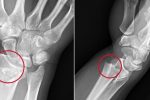

مو برداشتن استخوان؛ از علائم تا روش های درمان

در دنیای آسیبهای ارتوپدی، شاید هیچ عارضهای به اندازه "مو برداشتن استخوان" یا "ترک خوردن استخوان" با تصورات نادرست همراه نباشد.